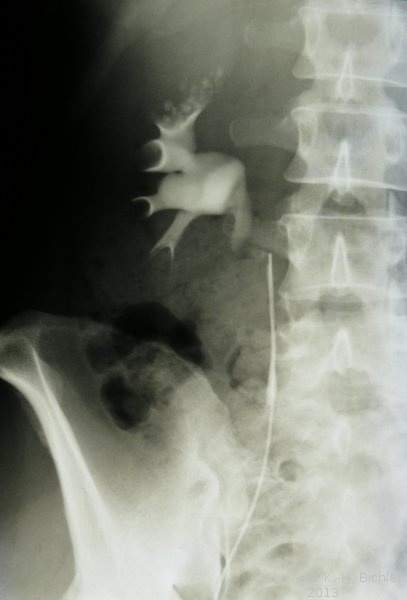

Die Diagnose wird ausgehend von der Sonographie gestellt (Abbildung 2). Zur Kontrolle der Abflussverhältnisse aus dem oberen Harntrakt ist ein i.v.-Pyelogramm empfehlenswert. Die typischen radiologischen Veränderungen im Pyramidenbereich der Markschwammniere werden im AUR erfasst (Abbildung 1). Das Röntgenbild zeigt die Kolbenförmigen, z.T. verplumpten Auftreibungen der Sammelrohre mit multipler Steinbildung.

Beispiele: Röntgenbilder (Abbildung 3).